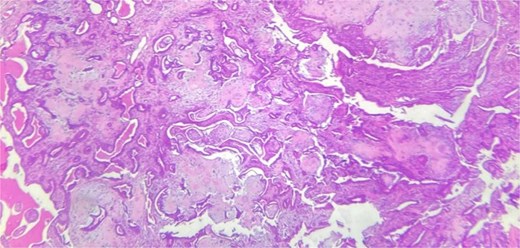

A 62-year-old Moroccan man, with no significant medical history, presented with a cheek swelling evolving over 9 months without associated symptoms. Clinical examination revealed a 1.2 cm nodular swelling in the cheek. It was mobile and skin-colored, without inflammatory signs. Lymph nodes and salivary glands were normal. An excisional biopsy of the mass was performed. Macroscopically, it was a 1.2 cm beige, friable to firm, rounded nodule. Microscopic examination showed a well-circumscribed benign tumor proliferation composed of cysts, tubules, and ducts, lined by a bilayered epithelium. The cells exhibited no nuclear atypia. The fibromyxoid and chondroid stroma (Fig. 4) allowed for diagnosis without additional techniques. There was no perineural invasion or vascular emboli, and surgical margins were clear. Postoperative recovery was uneventful, and no further follow-up or additional examinations were necessary.